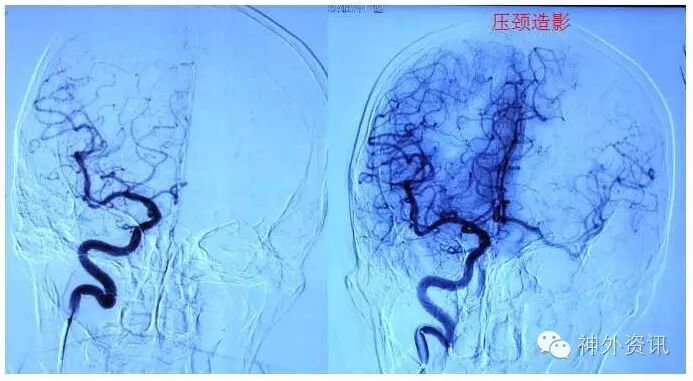

《后交通大动脉瘤》